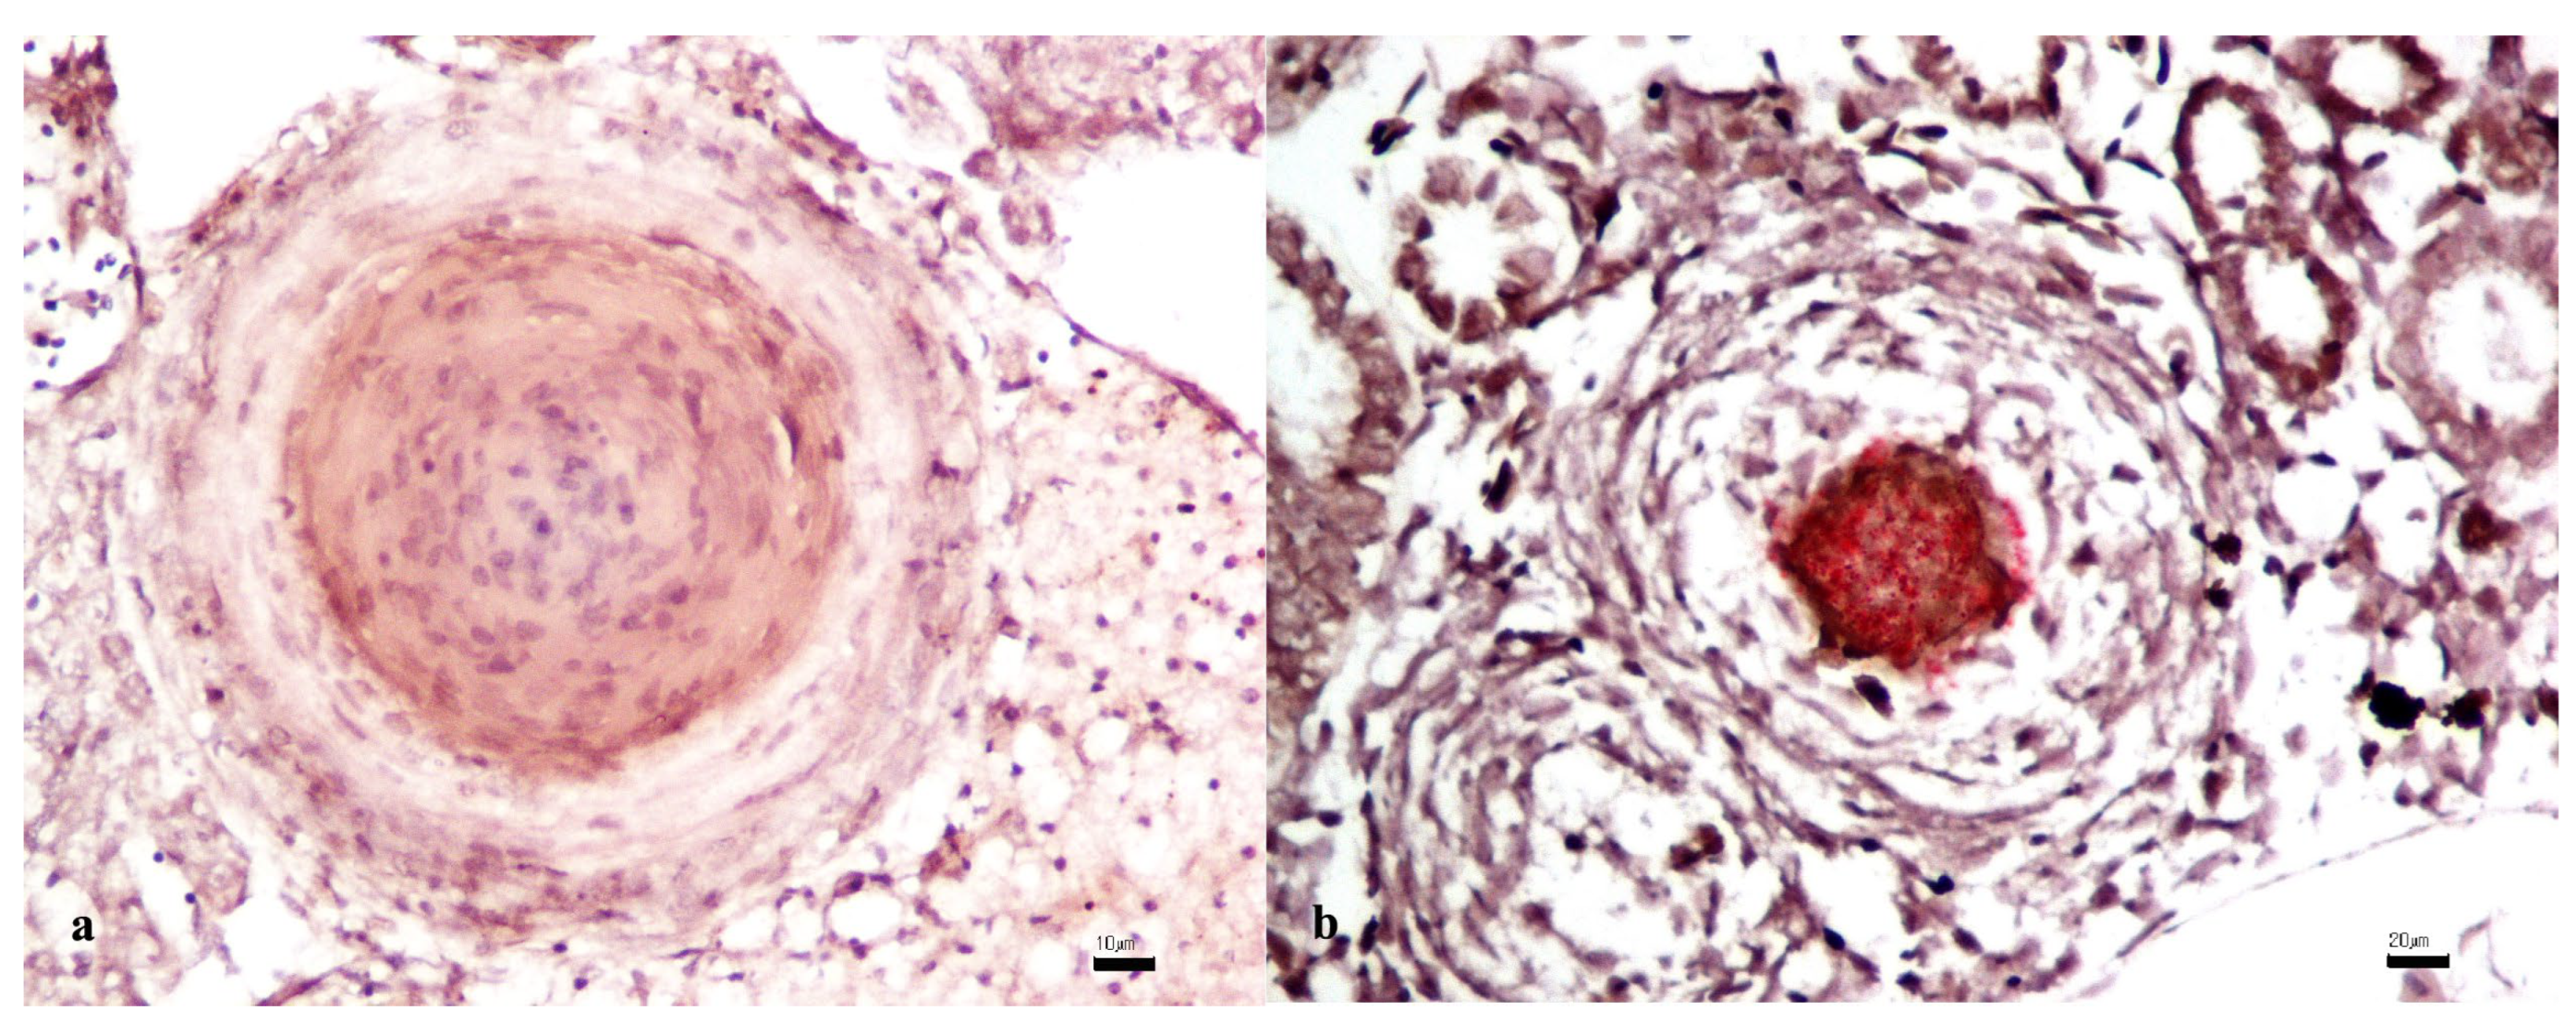

3.2. Histopathology

3.6. Association Between Histology and Mycobacteriun chelonae